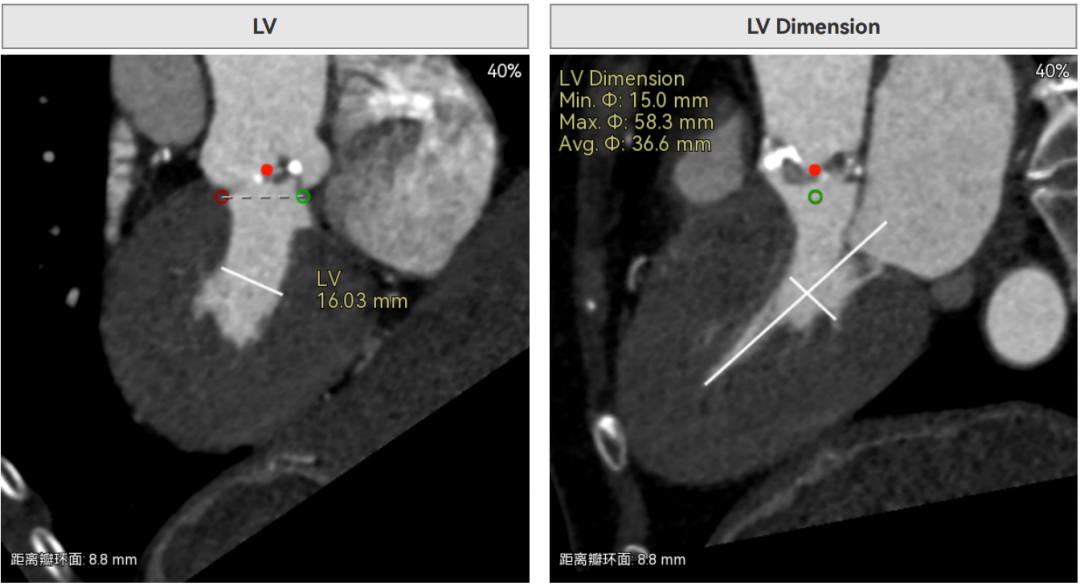

4.自杀左室:术前超声关键指标显示,患者左心室收缩末期内径仅 16mm,属于典型 “自杀左室”—— 左室腔极度狭小,意味着心脏循环储备功能已濒临临界状态。这一解剖特点带来致命性挑战:一是手术耐受性极差,球囊预扩张、瓣膜植入等操作过程中,任何短暂的血流阻断或心肌牵拉都可能诱发血压骤降、恶性心律失常,甚至直接导致低心排血量综合征或循环崩溃;二是与极小瓣环叠加后,血流动力学调节难度呈指数级上升,需在解除瓣口狭窄的同时,避免加重左室负荷,否则可能引发急性心衰,三是左室腔狭小导致瓣膜锚定空间不足,若瓣膜扩张后与左室流出道不匹配,可能加剧梗阻风险,进一步恶化循环功能。

经过赵元教授团队分析,拟右股动脉作为主入路,使用18mm球囊预扩,选择AV23号内联鞘版本Prostyle A®瓣膜进行释放。